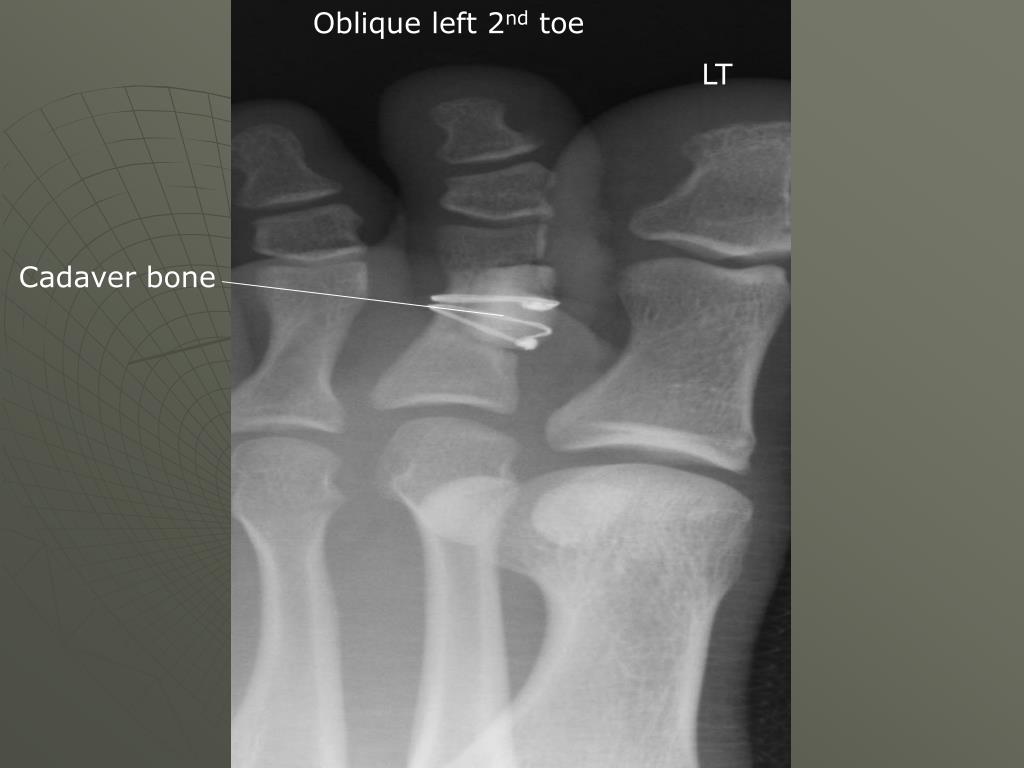

10. Oblique left 2nd toe LT Cadaver bone

9. Structures shown **** We do a medioblique: • An oblique projection of the phalanges • The Interphalangeal joints and 2nd -5th metatarsophalangeal joints open ***Distal phalanx to the distal end of the metatarsal • Toes should be separated from each other • Both soft tissue and bony trabeculation should be seen (techn)